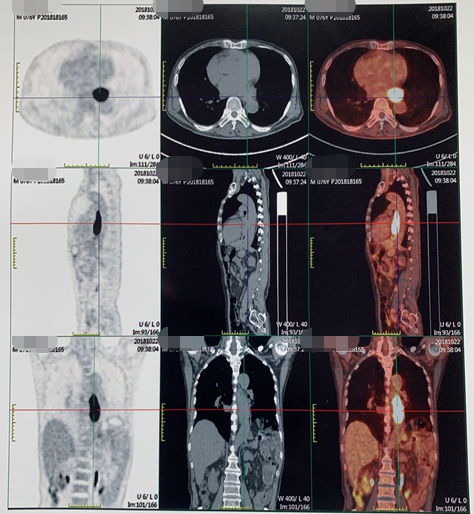

PET/CT(2018-10-22):食管中下段管壁增厚FDG代谢增高,吻合口下方肠壁FDG代谢增高灶;左上腹系膜区多发FDG代谢增高灶,考虑多发转移;后腹膜区及右侧髂血管旁多发小淋巴结FDG代谢轻度增高,倾向转移淋巴结。